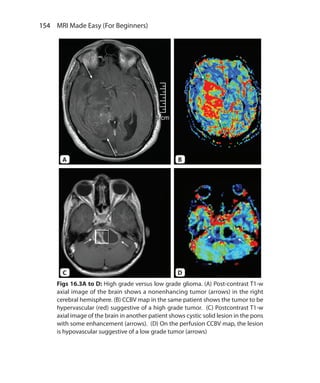

obtained

Fat and white matter are suppressed 3. CSF and water is suppressed

Mainly used in body imaging 4. Used in neuroimaging

Cannot be used in postcontrast

imaging as short T1 tissue are